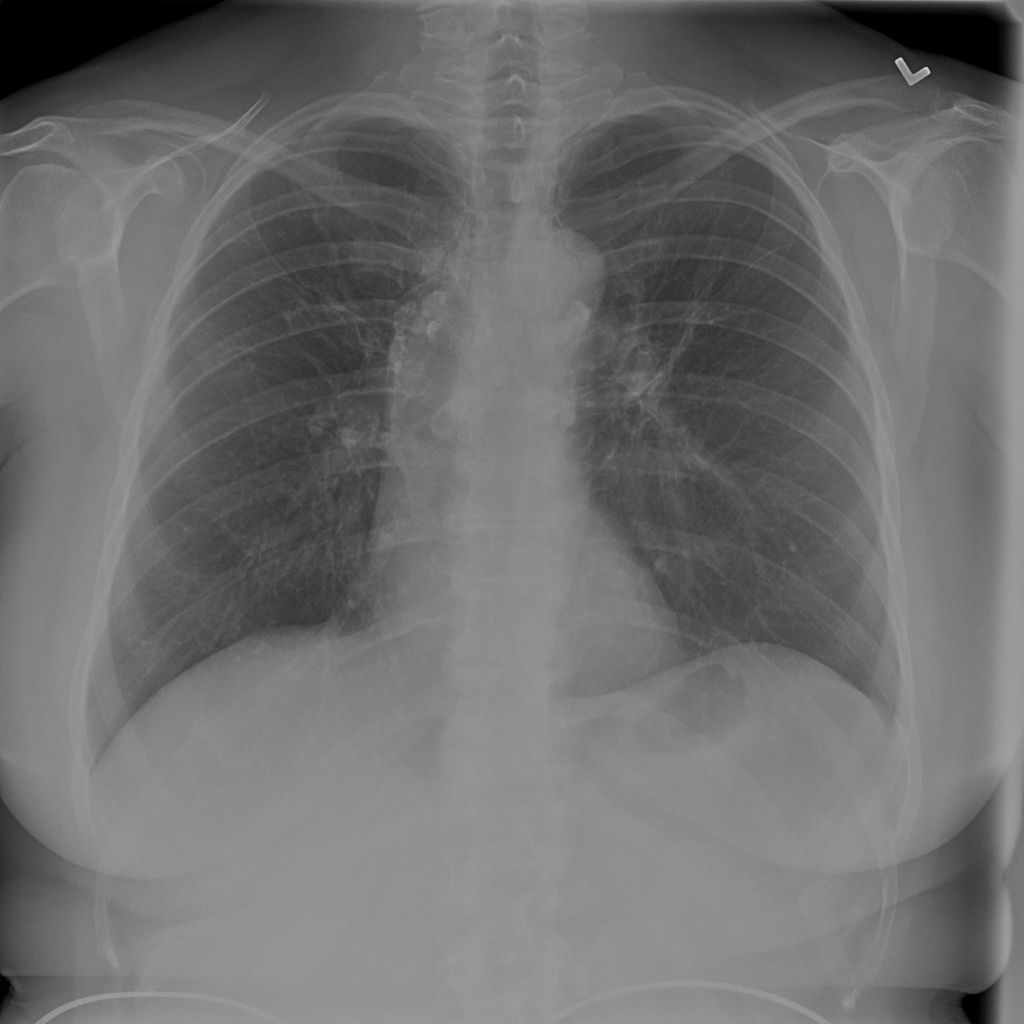

Showing up to 90 reference images for Nodule.

PAT-FB8F · IMG-000Nodule

PAT-FB8F · IMG-000

PA